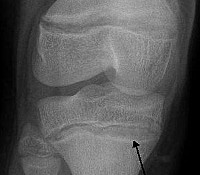

• Инструментальное. Основа аппаратного обследования — рентгенография крупных костей, где обнаруживаются признаки отложения токсиканта. На ЭКГ — снижение высоты зубца P, уменьшение интервала R-R, нарушение внутрисердечной проводимости. На УЗИ — увеличение размеров печени, селезенки, структурные изменения почечной паренхимы.